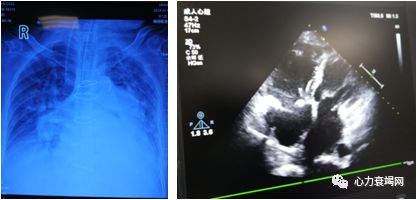

➤ 黄某某,女,52岁

➤ 2018-2-24 入院

1.风湿性心脏瓣膜病:二尖瓣狭窄并重度关闭不全、主动脉瓣狭窄并关闭不全、三尖瓣关闭不全、全心扩大、左房血栓、中重度肺动脉高压、房颤心功能IV级;

2.腹主动脉、双下肢动脉广泛血栓、狭窄;

3.肺部感染 双侧胸腔积液 呼吸衰竭;

4.腹腔积液;

5.重度营养不良”。

➤ 慢性右心衰竭原因:

左心瓣膜病变

肺动脉高压

三尖瓣关闭不全

➤ 治疗决策

手术2018-3-5

二尖瓣置换、主动脉瓣置换、三尖瓣成型、左房血栓清除、左心耳结扎、右房成型

➤ 2018-4-11 出院 康复治疗